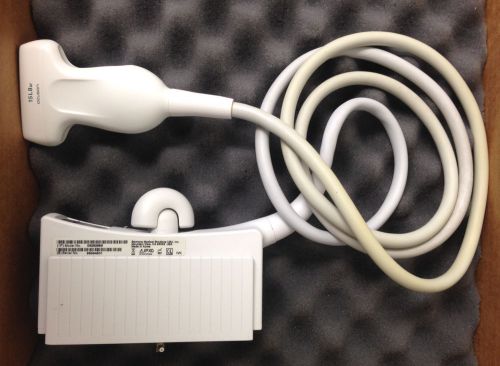

Ultrasound Transducer GE 10LB-RS Linear Vascular/Small Parts for GE Logic Book